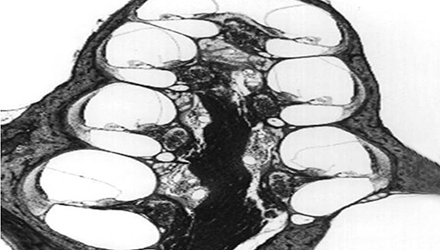

膜迷路積水致膜迷路脹破,內外淋巴液混合,刺激神經感覺細胞導致眩暈、耳鳴、耳聾,裂口愈合則病變暫時恢復。下圖左為前庭膜膨大,右圖為前庭膜破裂,內外淋巴交混。

上圖為內淋巴對比圖。左圖正常,右圖內淋巴積水